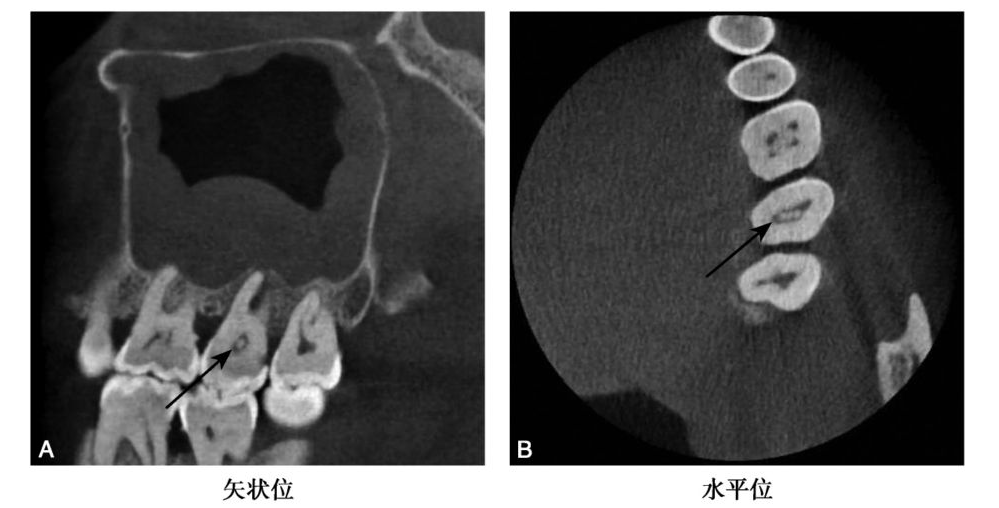

图2 B7髓腔髓石

CBCT示B7牙髓腔内可见高密度髓石影,矢状位示呈卵圆形,水平位示呈针状(黑色箭头)